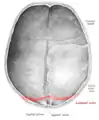

Lambdoid suture seen from above.